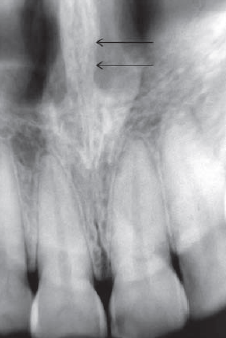

49. What is showing by arrow?

Mental Ridge (protuberance) On periapical radiographs of the mandibular central incisors, the mental ridge may occasionally be seen as two radiopaque lines sweeping bilaterally forward and upward toward the midline.

50. What is showing by arrow?